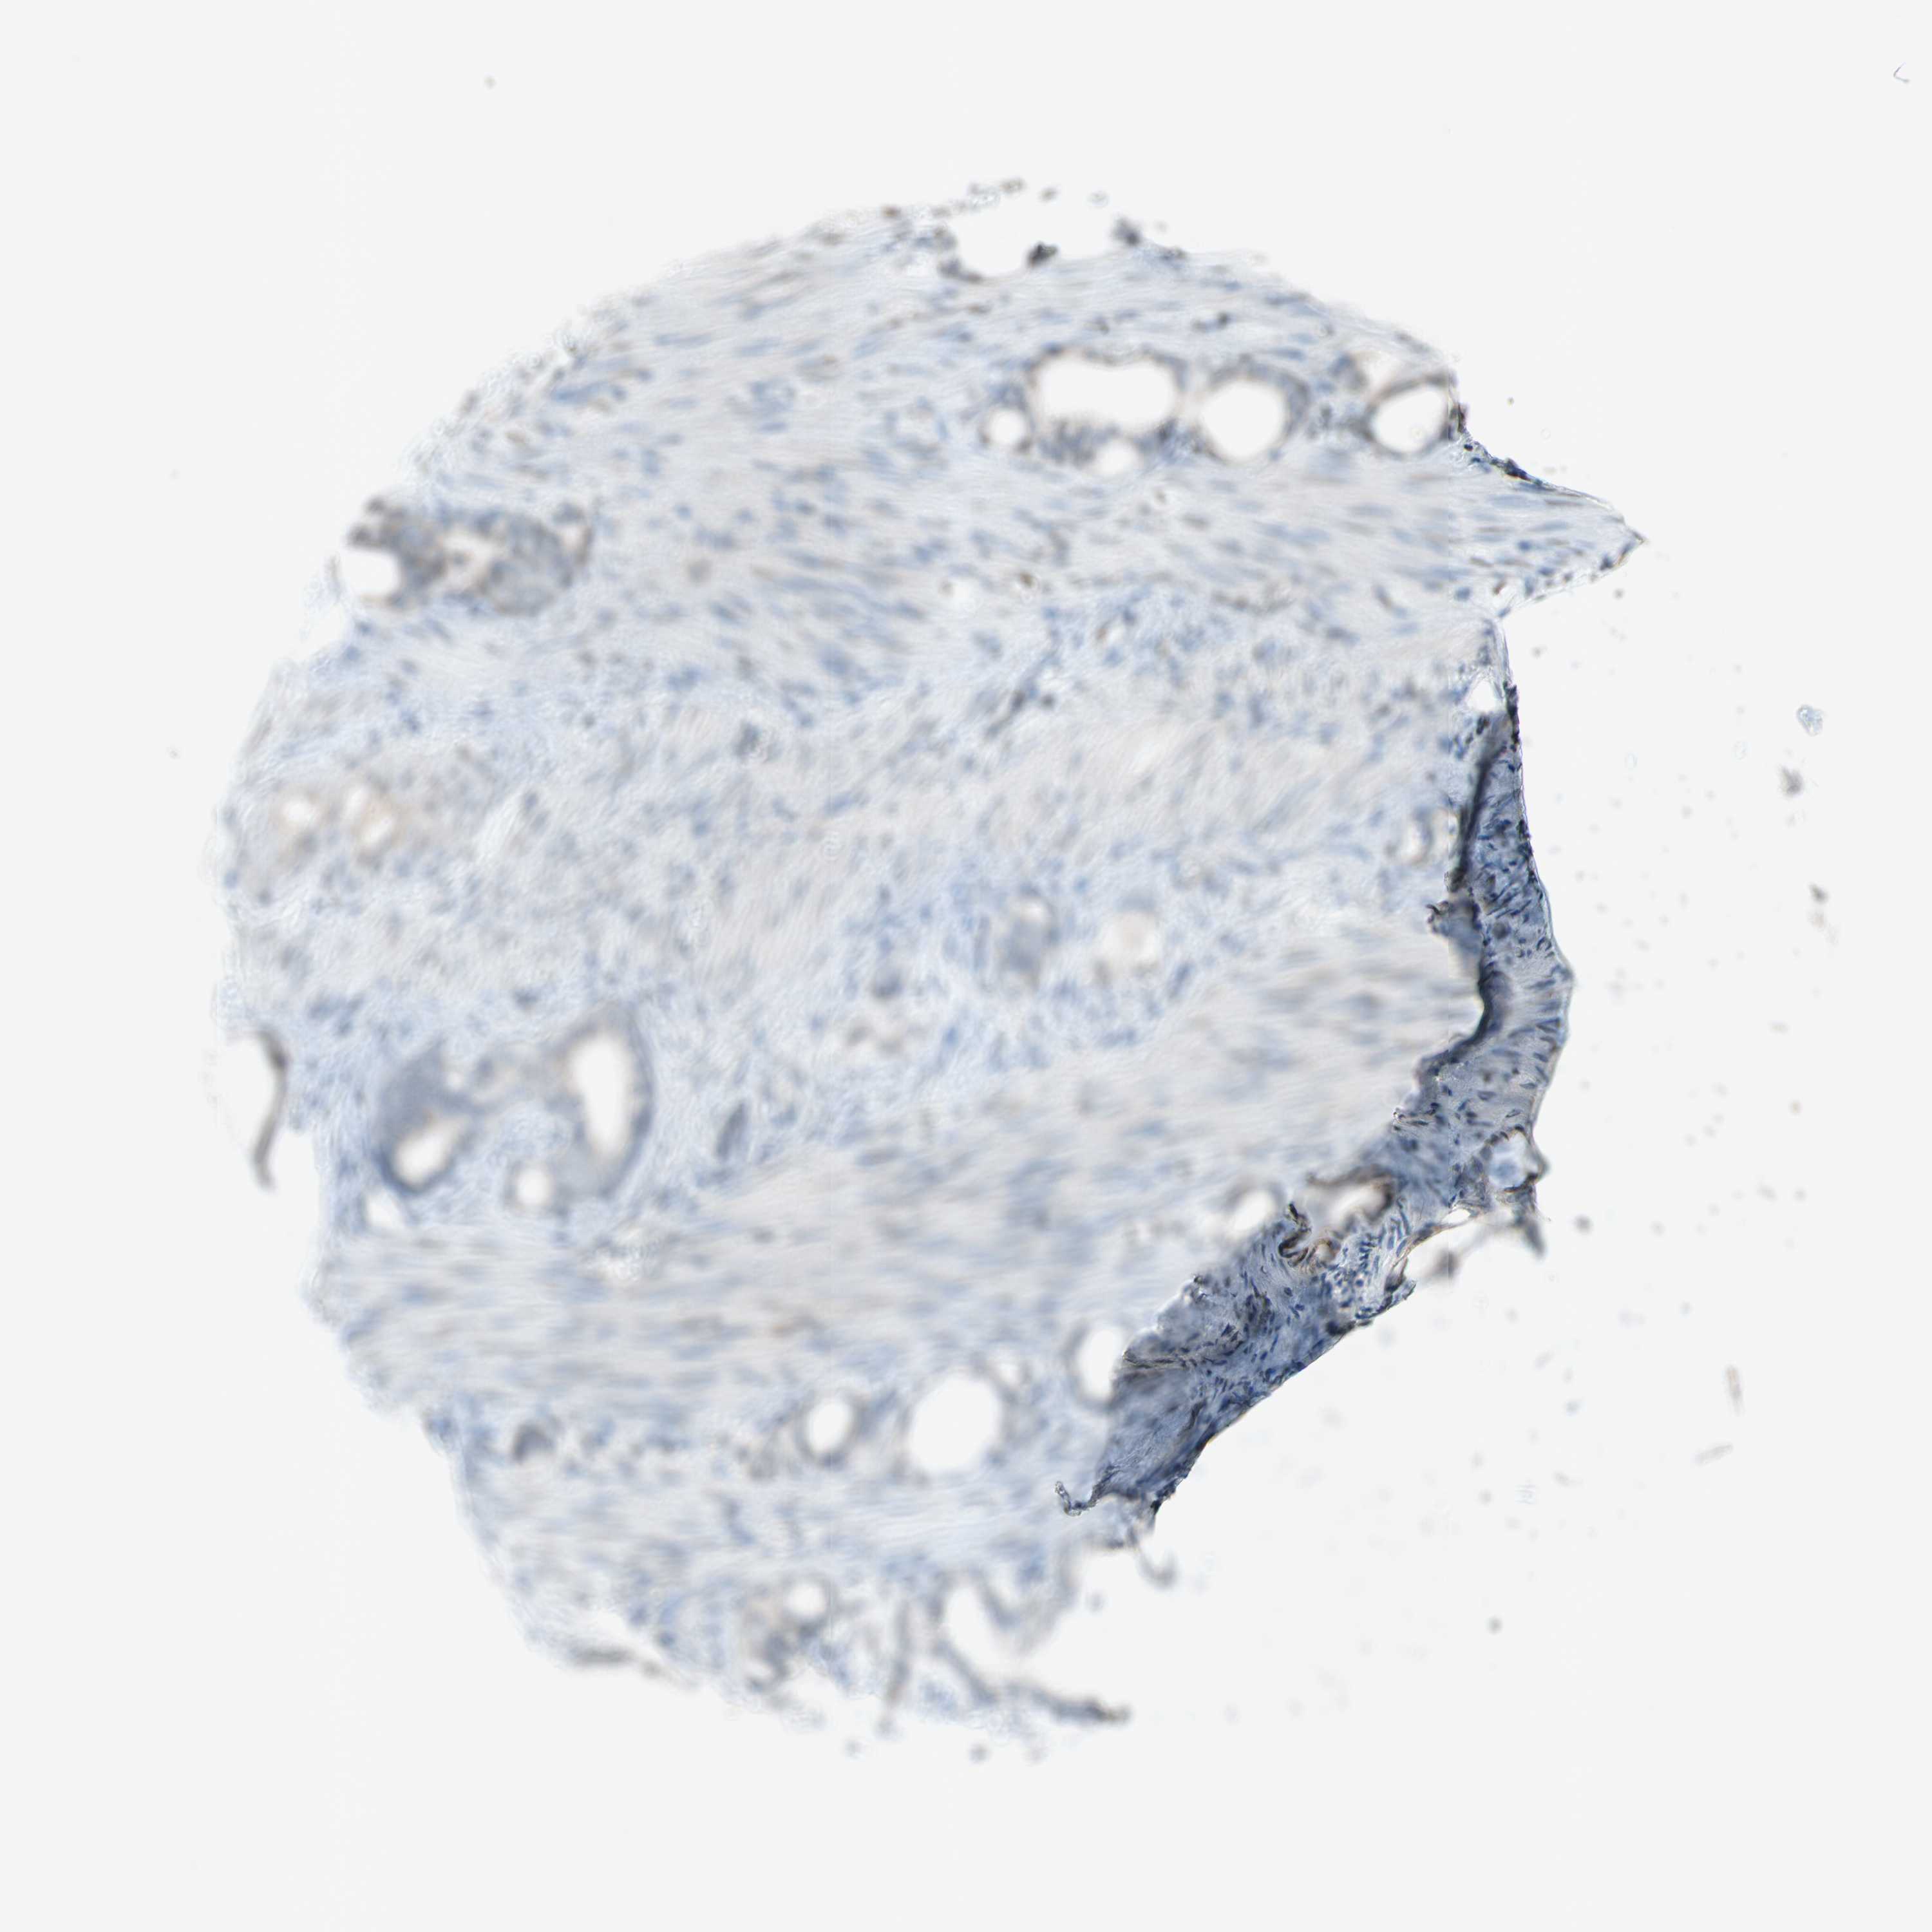

STOMACH CANCER - Protein expressioni

A mouse-over function shows sample information and annotation data. Click on an image to view it in a full screen mode. Samples can be filtered based on level of antibody staining by selecting one or several of the following categories: high, medium, low and not detected. The assay and annotation is described here.

Note that samples used for immunohistochemistry by the Human Protein Atlas do not correspond to samples in the TCGA dataset.

Antibody stainingi

Antibody staining in the annotated cell types in the current human tissue is reported as not detected, low, medium, or high, based on conventional immunohistochemistry profiling in selected tissues. This score is based on the combination of the staining intensity and fraction of stained cells.

Each image is clickable and will lead to virtual microscopy that enables deeper exploration of all samples and also displays staining intensity scores, fraction scores and subcellular localization as well as patient and tissue information for each sample.

Antibody HPA013166

Antibody CAB009789

Staining

High

Medium

Low

Not detected

Intensity

Strong

Moderate

Weak

Negative

Quantity

>75%

75%-25%

<25%

None

Location

Nuclear

Cytoplasmic/membranous

Cytoplasmic/membranous,nuclear

Adenocarcinoma, NOS

Adenocarcinoma, High grade